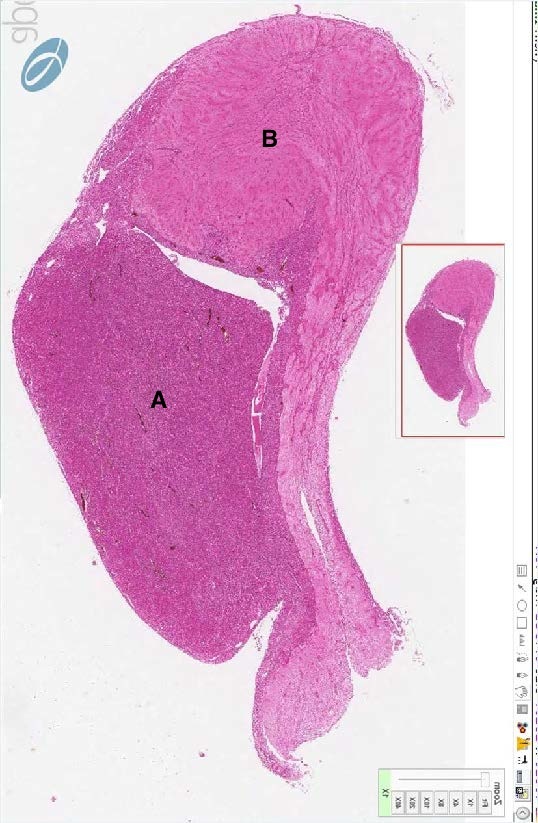

Identify B in this H&E cross section of a pituitary gland.

Posterior Pituitary (neurohypophysis)

Identify A in this H&E cross section of a pituitary gland.

Anterior Pituitary (adenohypophysis)